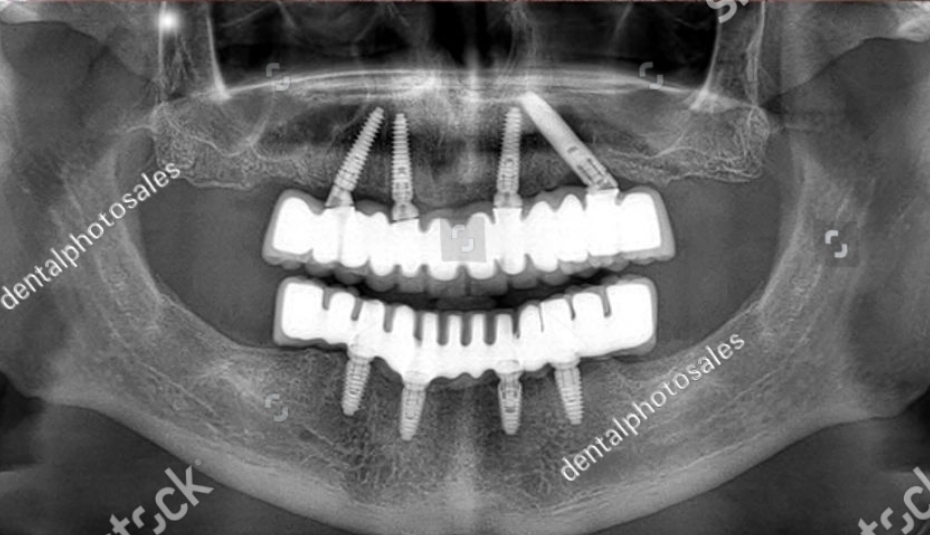

A case like this required collaboration—not just between prosthodontist and oral surgeon, but also her rheumatologist and general physician. We conducted a thorough CBCT scan, revealing significant maxillary bone resorption and close proximity to the sinuses, making implant placement in the posterior region challenging.

Using computer-guided implant placement, we placed six implants in the upper jaw—strategically avoiding sinus areas and ensuring maximum use of remaining bone. A flapless surgical approach helped minimise trauma, allowing for quicker healing and reducing discomfort.

Following the integration period, a custom-milled zirconia bridge was placed. It was screw-retained for retrievability and designed with concave intaglio surfaces for easier hygiene access.